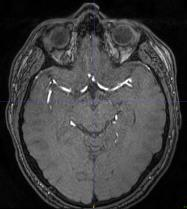

The use of deep learning techniques for 3D brain vessel image segmentation has not been as widespread as for the segmentation of other organs and tissues. This can be explained by two factors. First, deep learning techniques tend to show poor performances at the segmentation of relatively small objects compared to the size of the full image. Second, due to the complexity of vascular trees and the small size of vessels, it is challenging to obtain the amount of annotated training data typically needed by deep learning methods. To address these problems, we propose a novel annotation-efficient deep learning vessel segmentation framework. The framework avoids pixel-wise annotations, only requiring patch-level labels to discriminate between vessel and non-vessel 2D patches in the training set, in a setup similar to the CAPTCHAs used to differentiate humans from bots in web applications. The user-provided annotations are used for two tasks: 1) to automatically generate pixel-wise labels for vessels and background in each patch, which are used to train a segmentation network, and 2) to train a classifier network. The classifier network allows to generate additional weak patch labels, further reducing the annotation burden, and it acts as a noise filter for poor quality images. We use this framework for the segmentation of the cerebrovascular tree in Time-of-Flight angiography (TOF) and Susceptibility-Weighted Images (SWI). The results show that the framework achieves state-of-the-art accuracy, while reducing the annotation time by up to 80% with respect to learning-based segmentation methods using pixel-wise labels for training